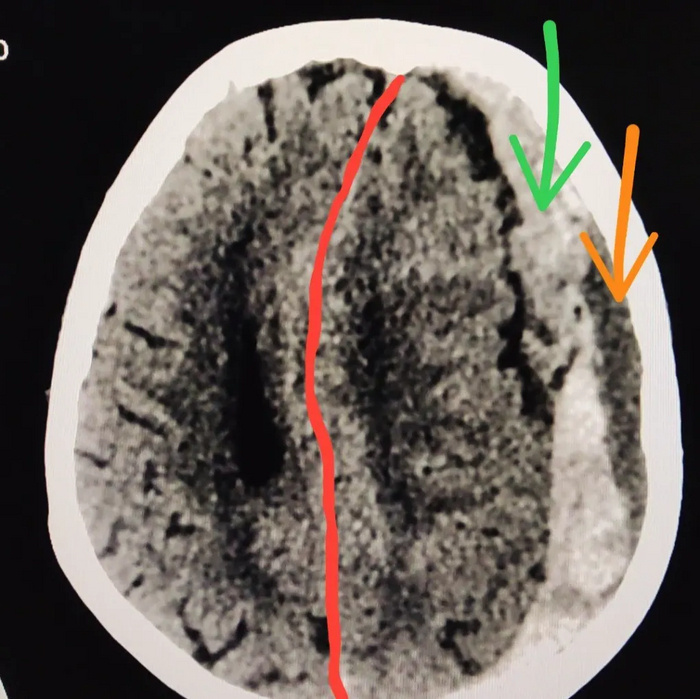

На КТ головного мозга субдуральная гематома слева (на картинке она справа, обведена красным цветом)

Со смещением срединных структур мозга (обозначено красной линией)

Также можно заметить что в гематоме есть кровь разной плотности. Под зелёной стрелкой свежее кровоизлияние, а под оранжевой старое кровоизлияние, которое произошло, возможно, днями или неделями ранее.